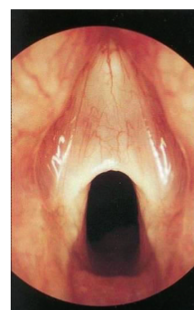

Laryngeal Web

- Question: A 2 -month- old baby brought to the clinic by his parent with history of weak cry since birth and stridor, there was no chocking. on examination scope was performed and the finding is displayed in the picture.

- Answer:

- A- what is the diagnosis?

- laryngeal web

- B- what is the management?

- laser excision and stent